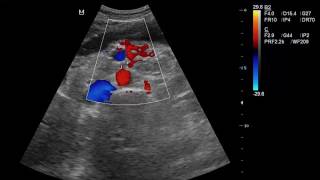

UKETS Clampless Technique in Open Revascularization of Acute Mesenteric Ischemia

Learn more: http://www.ctsnet.org/article/clampless-technique-open-revascularization-acute-mesenteric-ischemia.